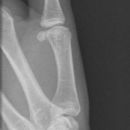

Mittelgliedbasisfraktur